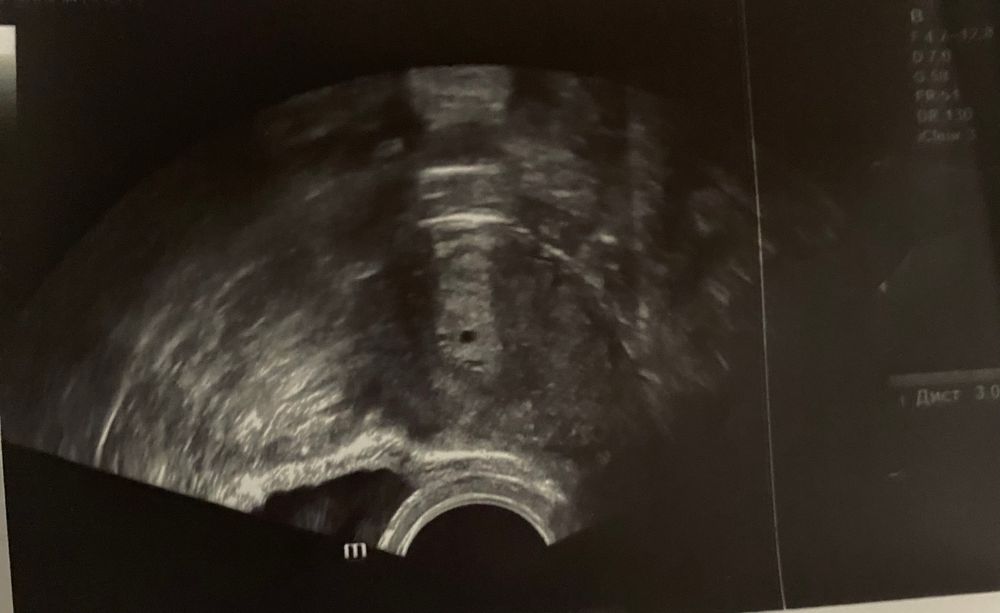

Все доброго времени суток! Была сегодня на первом УЗИ. Напугали меня жутко. Месячные последние были 24 декабря. По месячным сейчас 3 недели и 6 дней. Узистка сказала, что очень странно, что на таком раннем сроке есть плодное яйцо, типо ещё даже задержки не было (до неё 4 дня) а уже плотное яйцо 3мм, типо это ненормально, может какая-то ложная беременность или какое-то включение. Ещё напугала тем, что эндометрий маленький-11мм.

Очень странный врач узи. Нормальный эндометрий, для имплантации самое то. И совершенно не понятно, зачем делать на таком сроке узи. ПЯ видно, когда хгч выше 1000. Никто не поставит маточную беременность раньше.